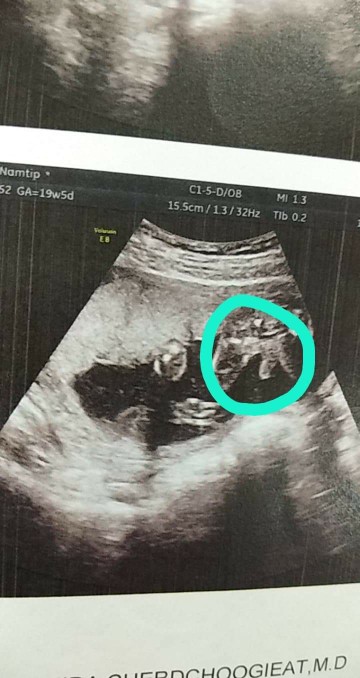

แบบนี้ หญิงหรือชายค่ะ

ชายค่ะ ปิกะจูชัดมาก